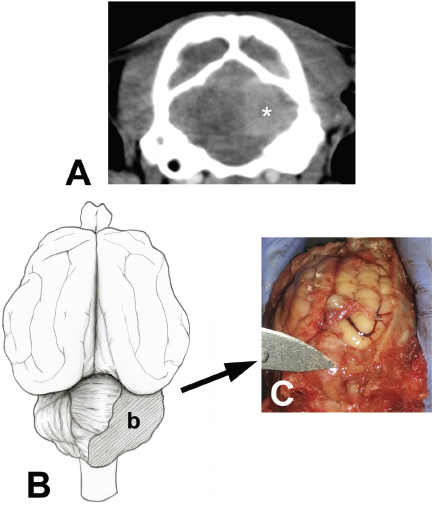

Additional tests included complete blood count, biochemical profile, FeLV/ Feline immunodeficiency virus (FIV) testing, cerebrospinal fluid analysis, and computed tomography (CT) of the head. Complete cell blood count showed no clinically significant abnormalities. Biochemical analysis results were within reference ranges. Cerebrospinal fluid indicated mononuclear and neutrophilic pleocytosis with normal total protein concentration (<0.25 g/l). A commercial immunoassay was used to test blood samples for Feline leukemia virus antigen and FIV antibodies (SensPERT FeLV Ag/FIV Ab Test Kit, Vet All Laboratories). The cat tested positive for FeLV and negative for FIV. Contrast CT scanning of the head revealed multiple heterogeneous hypodense areas in both cerebral hemispheres, mild ventriculomegaly, and a circular sharply marginated homogeneously hyperdense mass occupying the right cerebellar hemisphere (Fig. 1A). The animal was treated with trimethoprim-sulfamethoxazole (20 mg/kg every 12 hours) and prednisone (1 mg/kg every 24 hours) over 6 days due to the initial diagnosis of suspected systemic infection with neurologic signs or toxoplasmosis.

The cat responded poorly to therapy, and the owners requested humane euthanasia. A complete necropsy study was performed and postmortem macroscopic findings revealed a friable mass with regular edges of approximately 1.1 × 1.3 × 1.2 cm located in the right cerebellar hemisphere close to the vermis (Fig. 1B and 1C). On macroscopic examination, no abnormalities were observed in lung, heart, spleen, lymph node, large and small intestines. Cerebellar tissue sections were obtained for histopathological and immunohistochemical analyses. Cerebellar and cerebral tissue samples were fixed in 10% formaldehyde, subjected to automatic tissue processing, and then embedded in paraffin. Thin sections of 5 μm thickness were obtained and stained with hematoxylin and eosin.

Fig. 1. (A). Contrast computed tomography of the head of an 8-month domestic cat with signs of dysmetria and head tremors. Note the homogenous sharply marginated hyperdense mass (white asterisk) in the right caudal cerebral fossa, which was consistent with cerebellar neoplasia. (B). Schematic representation of the location and extent of the neoplastic mass (b) in the cerebellum of a feline of 8 months of age. (C): Postmortem photographic image of the lesion. The neoplastic lesion included the vermis and right cerebellar hemisphere caudal to the primary fissure was later confirmed as lymphoma.